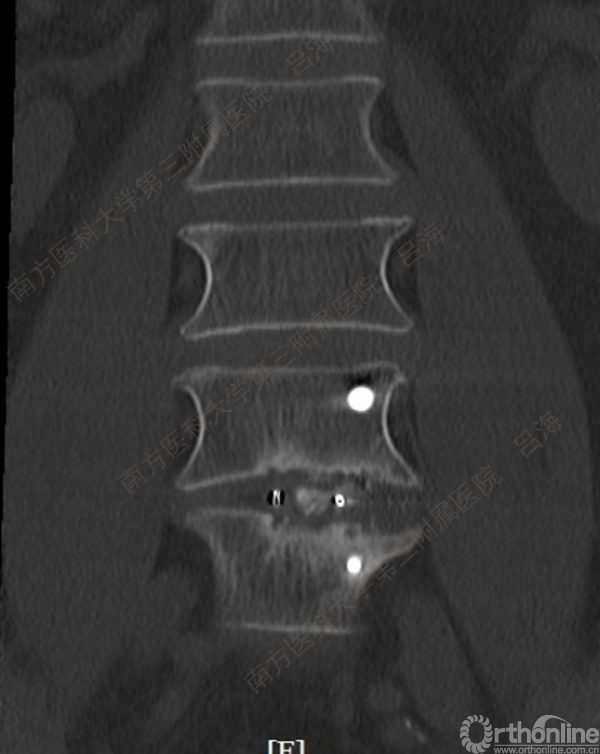

随着社会老龄化进程加快,胸腰椎退行性病变的治疗已经成为脊柱学术界的一个热点话题。MIS-TLIF手术可以治疗多种不同的胸腰椎退行性疾病,南方医科大学第三附属医院吕海教授结合病例为我们一一展示了该术式在治疗不同胸腰椎疾病时的具体手术过程。